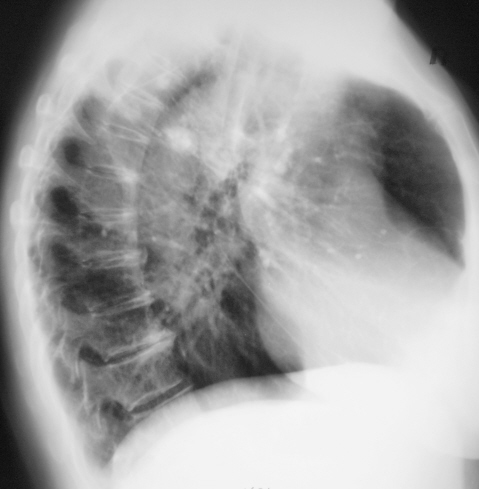

Произведены томограммы.

Какие будут мнения?

Конгломерат извести. При отсутсвии клиниколабораторных данных за активность туб. процесса я бы рискнул оставить пациента в покое на 3 месяца с последующим рентгенологическим контролем.

Я согласен с Вами коллега, мы так и поступили - "оставили его в покое", с последующи контролем через 6 месяцев.

Валентини Львович, в целом впечатление о туберкулёме в стадиии обострения ( инфильтрации?).Рекомендовал бы консультацию в Противотуберкулёзном диспансере!